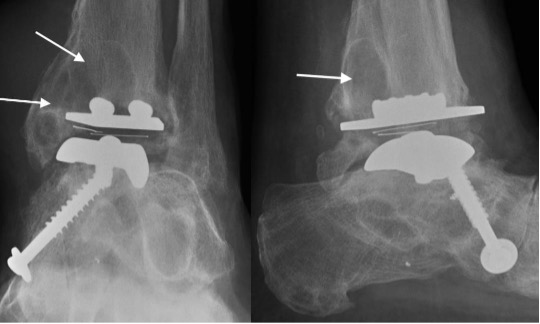

Failing TAR with progressive periprosthetic lucency (arrows)

Metalware failure